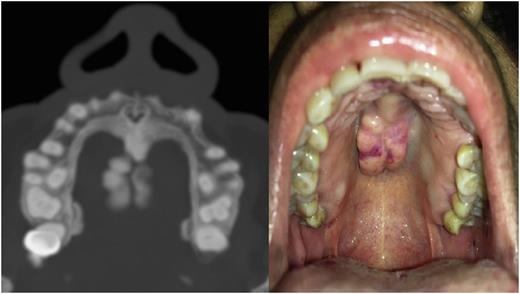

Material and methods Anemic adults with HHT based in Curaçao clinical diagnosis criteria, three to four from: a) telangiectases, b) epistaxis, c) visceral involvement and d) direct family history (Am J Med Genet 2009;91:66-67); and positive endoscopic study with moderate to severe GIT bleeding; some patients had a full body CT Scan and showed telangiectasi in al GIT as in Figure 1, the bone window reveal fill blooded telangiectasia. Thalidomide was initiated at 100 mg daily for a month and increased to 200 mg daily if tolerated for 12 months; aspirin 100 mg daily for thrombosis prevention; and omeprazole 20 mg with sucralfate 1 gr twice a day for GIT mucosal protection; transfusion to maintain hemoglobin level at 7-8 g/L and iron carboxymaltose to increase Hb levels and maintain ferritin above 50 ng/mL End points before and after treatment: a) number of episodes of GIT bleeding, b) number of red blood cells transfusions, and c) hemoglobin levels.